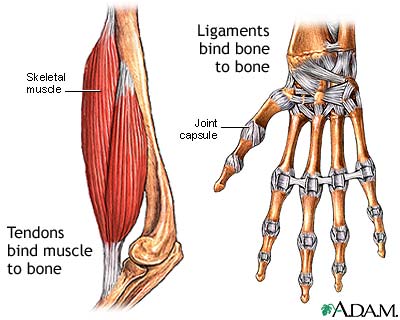

Tendons are the fibrous structures that join muscles to bones. When these tendons become swollen or inflamed, it is called tendinitis. In many cases, tendinosis (tendon degeneration) is also present.